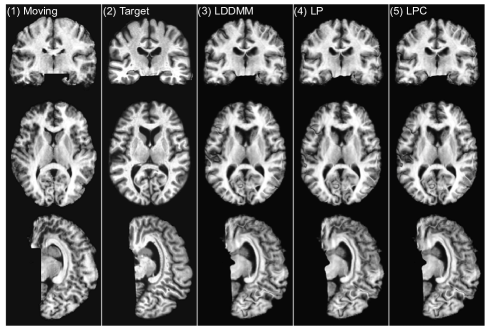

In this experiment, we use a sliding window stride of 14 for both the prediction network and the correction network during evaluation. We mainly compare the following three LDDMM-based -methods: (i) the numerical LDDMM optimization approach (LO) as implemented in PyCA, which acts as an upper bound on the performance of our prediction methods; and two flavors of Quicksilver: (ii) only the prediction network (LP) and (iii) the prediction+correction network (LPC). Example registration cases are shown in Fig. 9.

LO is the algorithm that our predictive registration approaches (LP and LPC) are based on. Hence, LP and LPC are not expected to show improved performance with respect to LO. However, similar performance for LP and LPC would indicate high quality predictions. Indeed, Table 3 shows that our prediction+correction approach (LPC) performs similar (with respect to the other registration methods) to LO. A slight performance drop with respect to LO can be observed for LPC and a slightly bigger performance drop for LP, which only uses the prediction model, but no correction model.

To assess statistical equivalence of the top performing registration algorithms we performed paired two one-sided tests (paired TOST) [71] with a relative threshold difference of 2%. In other words, our null-hypothesis is that methods show a relative difference of larger than 2%. Rejection of this null-hypothesis at a significance level of α=0.05/204𝛼0.05204\alpha=0.05/204 then indicates evidence for statistical equivalence. Table 4 shows the paired TOST results. For a relative threshold difference of 2% LPC can be considered statistically equivalent to LO for all four datasets and to many of the other top methods (e.g., LPC vs. SyN on MGH10 and IBSR18).

Overall, these statistical tests confirm that our prediction models, in particular LPC, are highly competitive registration algorithms. Computational cost, however, is very small. This is discussed in detail in Sec. 3.4.

3.2.3 Choosing the correct “correction step”

As shown in Sec. 3.2.2, LPP, LPC2 and LPC3 all result in label overlapping scores which are similar to the label overlapping scores obtained via LPC. This raises the question which method should be preferred for the correction step. Note that among these methods, only LPC is specifically trained to match the LDDMM optimization results and in particular to predict corrections to the initial momentum obtained by the prediction model (LP) in the tangent space of the moving image. In contrast, LPP, LPC2 and LPC3 lack this theoretical motivation. Hence, it is unclear for these methods what the overall optimization goal is. To show what this means in practice, we computed the determinant of the Jacobian of the deformation maps (Φ1superscriptΦ1\Phi^{-1}) for all voxels for all four registration cases of [33] inside the brain mask and calculated the histogram of the computed values. Our goal is to check the similarity (in distribution) between deformations generated by the prediction models (LP, LPC, LPP, LPC2, LPC3) in comparison to the results obtained via numerical LDDMM optimization (LO).